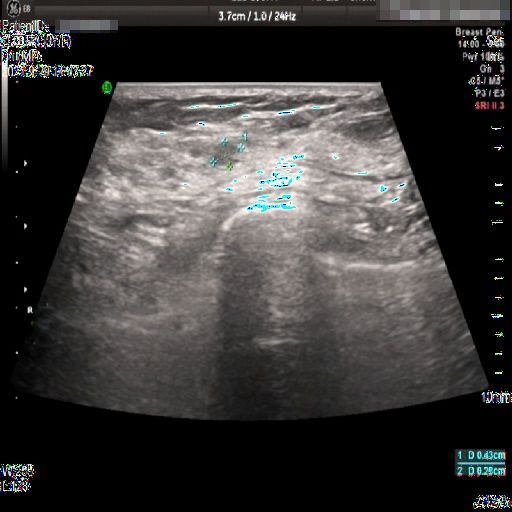

Images with certain annotations are considered noisy images in the context of the noise removal task, and corresponding images without these annotations are considered clean. Some typical images with various annotation are provided in Fig. 1.

The vascular flow annotation is not an additional labeling feature meant to simplify identification. Rather, it serves as a bounding box that identifies the specific area of the image being examined by the ultrasound flowmeter. However, to keep things simple, we will continue to call it a form of annotation. The presence of this annotation indicates that the relevant examination has been conducted.

Figure 1: Images with various annotations. (a) body marker annotation, (b) radical line annotation, (c) vascular flow annotation.